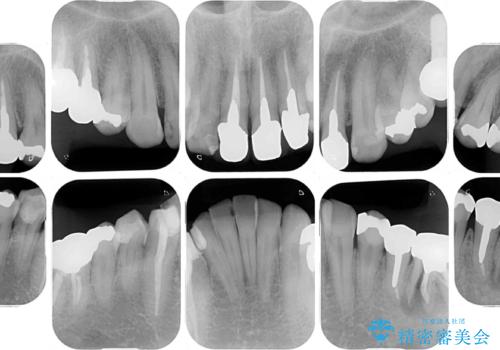

目立つ金属をすべてセラミックに 全顎的メタルフリー治療

- 黄ばんだ前歯や目立つ奥歯の銀歯をきれいにしたいとのことで来院された患者様です。

欠損している歯や、割れてしまって抜歯の必要な歯などがあり、咬合力が強いため欠損部はインプラント補綴を前提に治療を行うこととしました。

しかしながら、左下の抜歯部位は骨欠損が著しく大きく、多大な垂直的骨造成を要するため、3歯を支台としたブリッジによる補綴治療とし、右下のみをインプラント補綴としました。

小さい修復物の銀歯が装着されている歯はセラミックインレーにて、その他はオールセラミッククラウンにて補綴治療を進めることとしました。